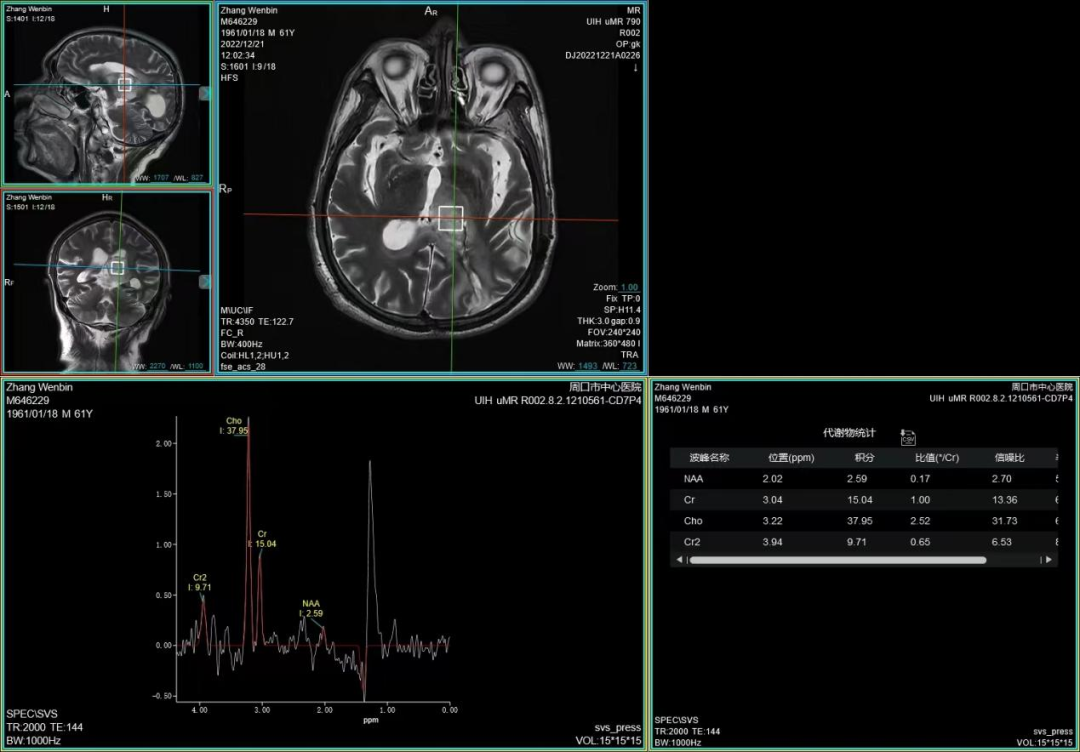

(颅脑波谱成像)

周口市中心医院磁共振室现已全面开展各项磁共振高级功能成像(包括SWI、PWI、BOLD、MRS、DTI等)、胎儿、乳腺、心脏、颞颌关节、动脉高分辨血管壁分析以及周围神经等检查,陆续开展磁共振介入和磁共振高级科研临床应用。磁共振功能成像广泛应用于临床各科,如神经内外科、肝胆内外科、心内科、小儿科、妇产科、泌尿科、肿瘤内外科等临床各个学科,这些极其优秀的特色MR成像技术,大大提高临床疑难疾病的诊断符合率,更有助于临床医生更准确有效及时的治疗,让患者得到更优质的康复。比如,DTI用于脑肿瘤对正常白质纤维束的侵占,术前和术后对于治疗效果的评估,可以更准确地反映白质纤维束的空间走向。在心血管领域突破了心脏禁区,可全面评估,心脏大血管解剖结构成像、心肌功能分析等全方位的检查研究,大大方便了中老年心脏病患者。在体部领域实现了肝脏三维容积超快速多期动态增强检查,可以敏感发现早期微小肝癌,不会遗漏边缘部位和微小病变。充分利用GE 3TMR“乳腺微观成像”高分辨展示乳腺结节、导管及淋巴结转移;“磁共振灌注成像”界定急性脑梗塞的缺血半暗带;“波谱成像”能真正在活体(病人)上分析化学成分。因此,努力提升MRS、SWI、DTI、PWI、CEMRA、腹部MR平扫及增强等MR功能成像业务,极大程度地避免了病人要到外地就医问题,也进一步提升了科室技术水平,并能获得良好的社会效益和经济效益。MR引导下穿刺活检及介入治疗。